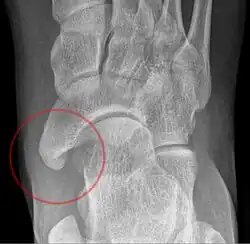

-

Type 2 -